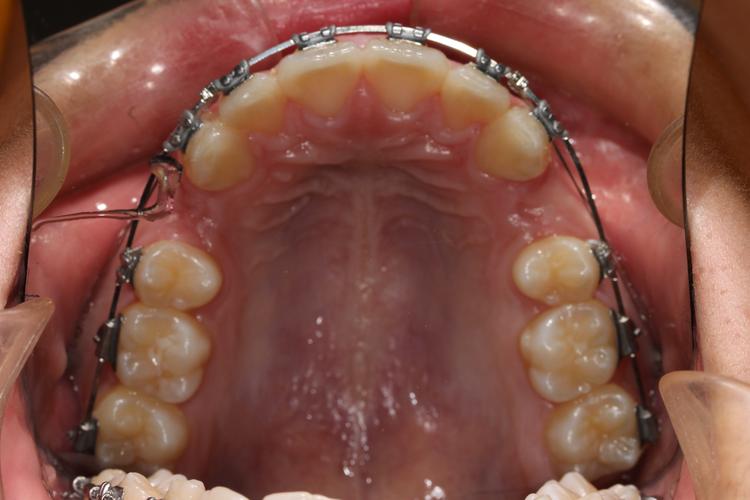

正畸种植钉的主要作用是在治疗期间提供“锚点”,当牙齿移动完成后,其支抗使命已完成,长期留存可能带来潜在风险:一是种植钉作为异物,若周围组织包裹过深或出现炎症,可能影响口腔健康;二是取出时机需与正畸整体方案同步,通常在拆除固定矫治器前或后,确保牙齿位置稳定、支抗需求解除,取出前,医生需通过临床检查和影像学评估(如根尖片或CBCT),确认种植钉周围无炎症、松动度适中,且与牙根、神经管等重要结构保持安全距离,避免取出过程中损伤邻牙或组织。

医生需详细检查种植钉周围软组织情况,观察是否有红肿、渗液等感染迹象;通过影像学检查明确种植钉的位置、方向及与周围骨组织、牙根的关系,判断取出难度,向患者说明取出过程(通常5-10分钟)、可能的不适感(如轻微酸胀、牵拉感)及术后注意事项,缓解患者紧张情绪。

用镊子或专用器械轻轻夹住种植钉头部,进行颊舌向、近远中向的轻柔晃动,评估其松动度,若治疗结束后已达到自然松动状态(通常植入后6-12个月,周围骨改建完成,种植钉与骨组织间出现间隙),取出阻力较小;若仍较稳固,需借助器械辅助。